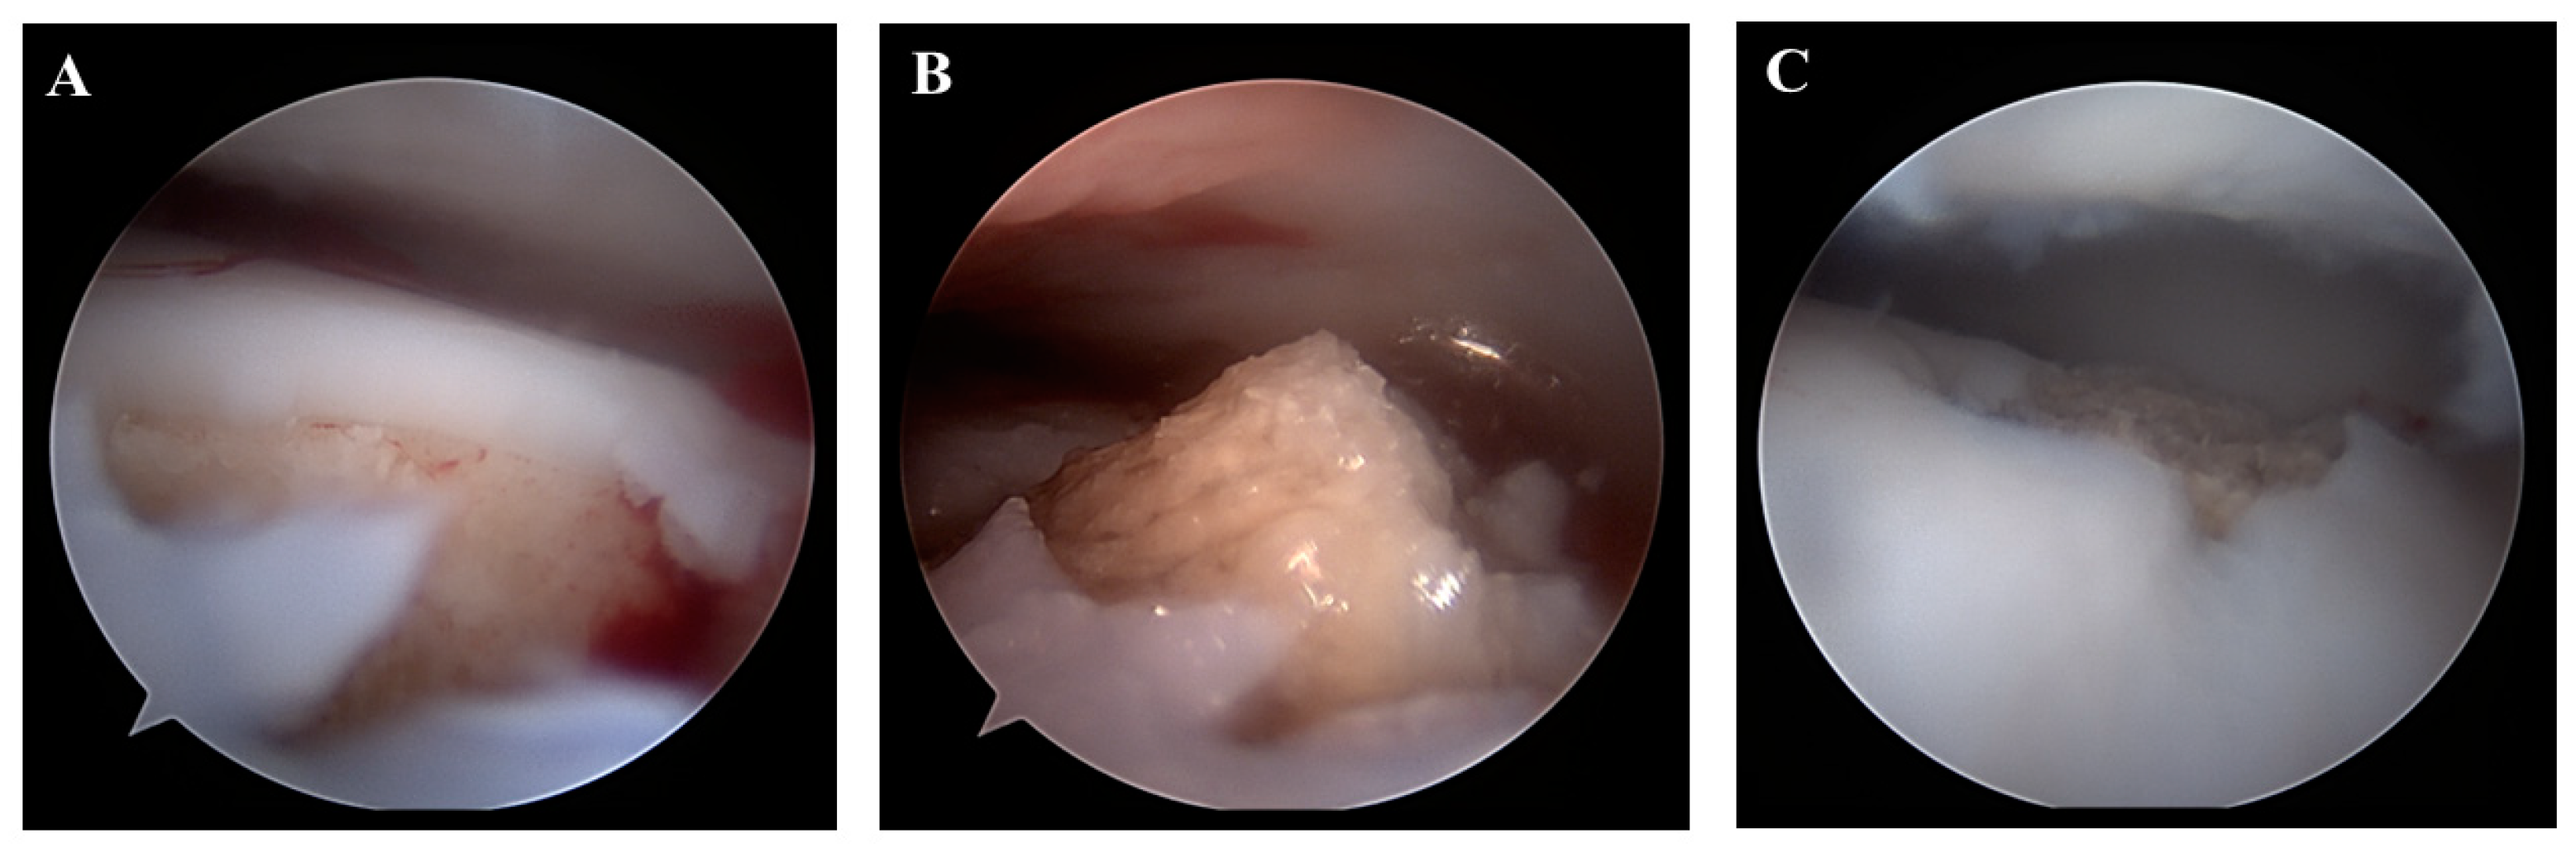

2.2. Surgical Techniques